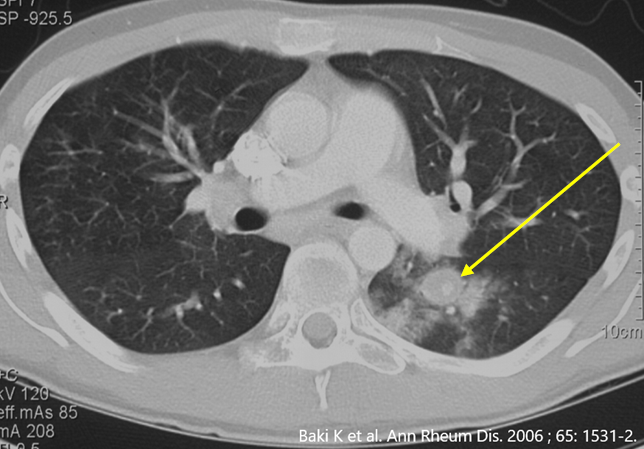

Das Behçet Syndrom (BS) ist ein Chamäleon. Bei klassischer klinischer Präsentation ist das BS einfach zu diagnostizieren, bei atypischer Krankheit kann es zu einer jahrelangen Verzögerung bis zur Diagnose kommen (siehe Publikationsliste). Das BS kann alle Gefässtypen befallen, von grossen Arterien über mittlere und kleine Gefässe bis zu grossen Venen wie die Hohlvenen des Rumpfes. Die gefährlichsten Formen finden sich im jungen Erwachsenenalte, beispielsweise eine Entzündung der Lungengefässen (*), der Beinarterien oder ein Hirnbefall.